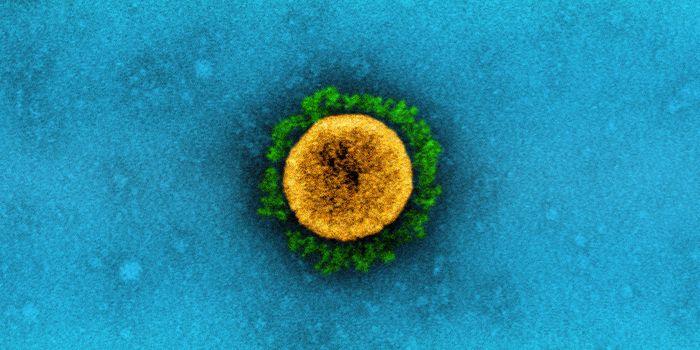

JUL 06, 2020MicrobiologyThe pandemic coronavirus has caused a wide range of different symptoms, and as time goes on, we may find that it can hav ...

JUL 05, 2020Cell & Molecular BiologyThe pandemic virus SARS-CoV-2 enters the body through the respiratory system to cause the illness COVID-19. But we know ...

JUN 29, 2020MicrobiologyVaccines that contain live attenuated viruses may be giving people some protection from serious cases of COVID-19 that i ...

FEB 22, 2021MicrobiologyReporting in Science, researchers have created an antiviral nasal spray that could help us get the COVID-19 pandemic und ...

SEP 01, 2021MicrobiologyIt's been generally assumed that people who get infected with SARS-COV-2 will develop antibodies to the virus, which cau ...

MAR 18, 2020MicrobiologySARS-CoV-2 is a coronavirus that causes an illness called COVID-19. There are now well over 210,000 confirmed cases worl ...